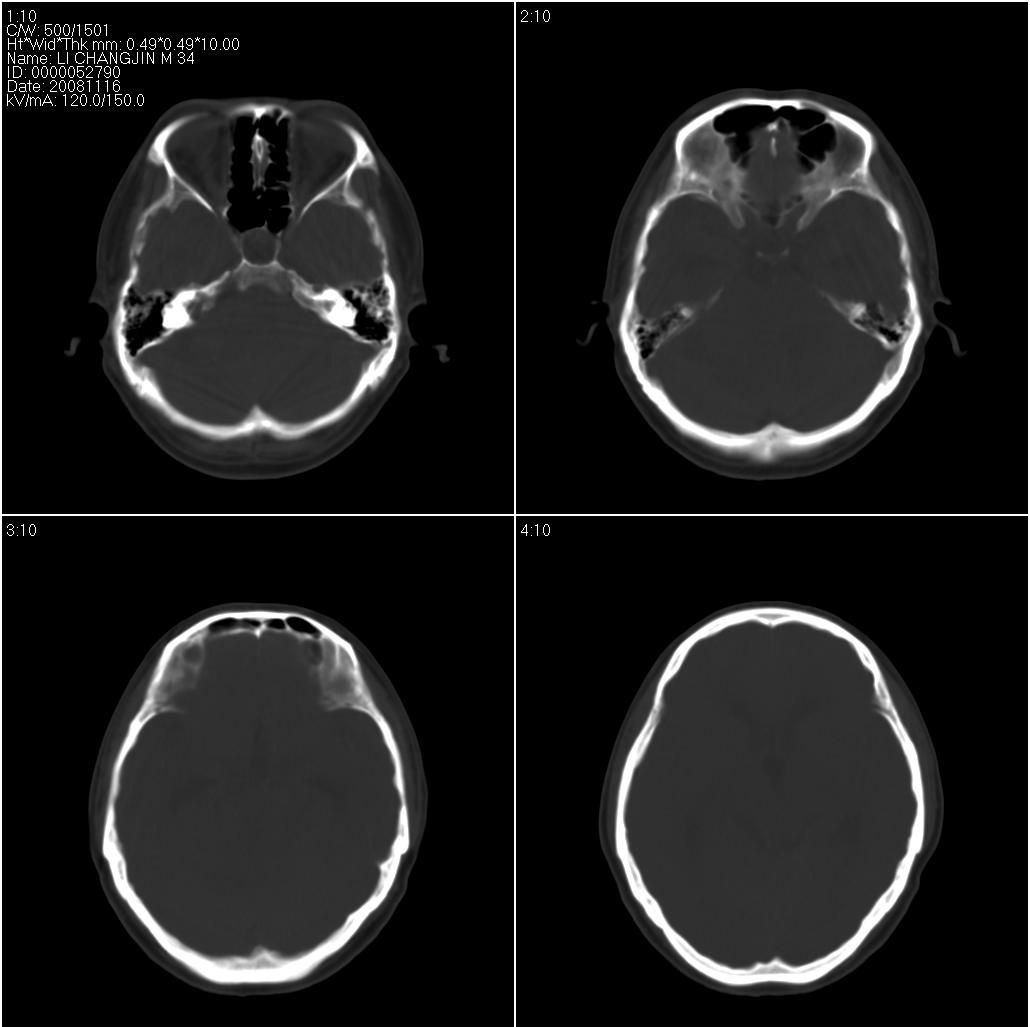

标题: CT16665:男,34岁。近来发现视力不好、眼花。 [打印本页]

标题: CT16665:男,34岁。近来发现视力不好、眼花。

支持右侧小脑半球占位性病变伴梗阻性脑积水。建议增强,上传骨窗,除外听神经瘤

看到骨窗了,右侧内听道扩大(再往下扫一层),支持听神经瘤

现在有骨窗了,内听道口好像被开挖了一样,支持考虑听神经瘤先

右侧桥小脑角区占位性病变,内听道扩大,骨质似见破坏,考虑为听神经瘤

右侧内听道扩大,支持听神经瘤

1)右侧听神经瘤。2)脑积水(梗阻性)。3)空蝶鞍。